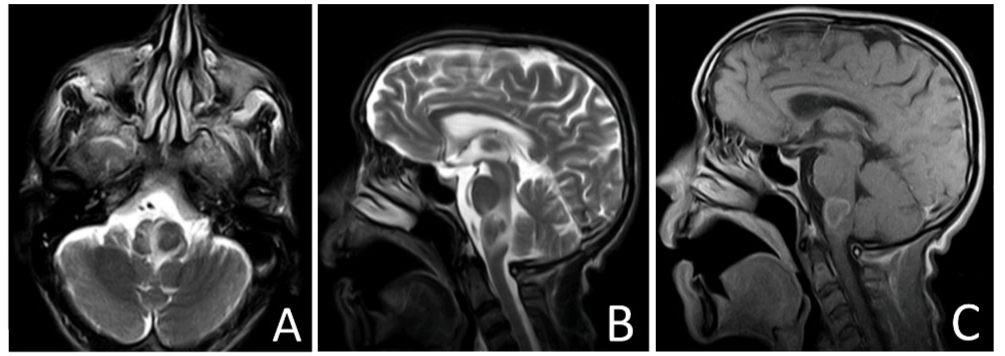

At the 2-month follow-up, the patient showed significant improvement in dysphagia, nausea, and vomiting. Subsequent visits improved gait and balance. A follow-up MRI at 12 months after completing the antituberculosis regimen showed complete resolution of the lesion in the lateral medulla (Fig. 2).

Fig. 2. Axial T2 (A), Sagittal T2 (B) and Sagittal (T1 post contrast) images of the brain taken after 9 months of anti TB medication showing a complete resolution of the medullary lesion.